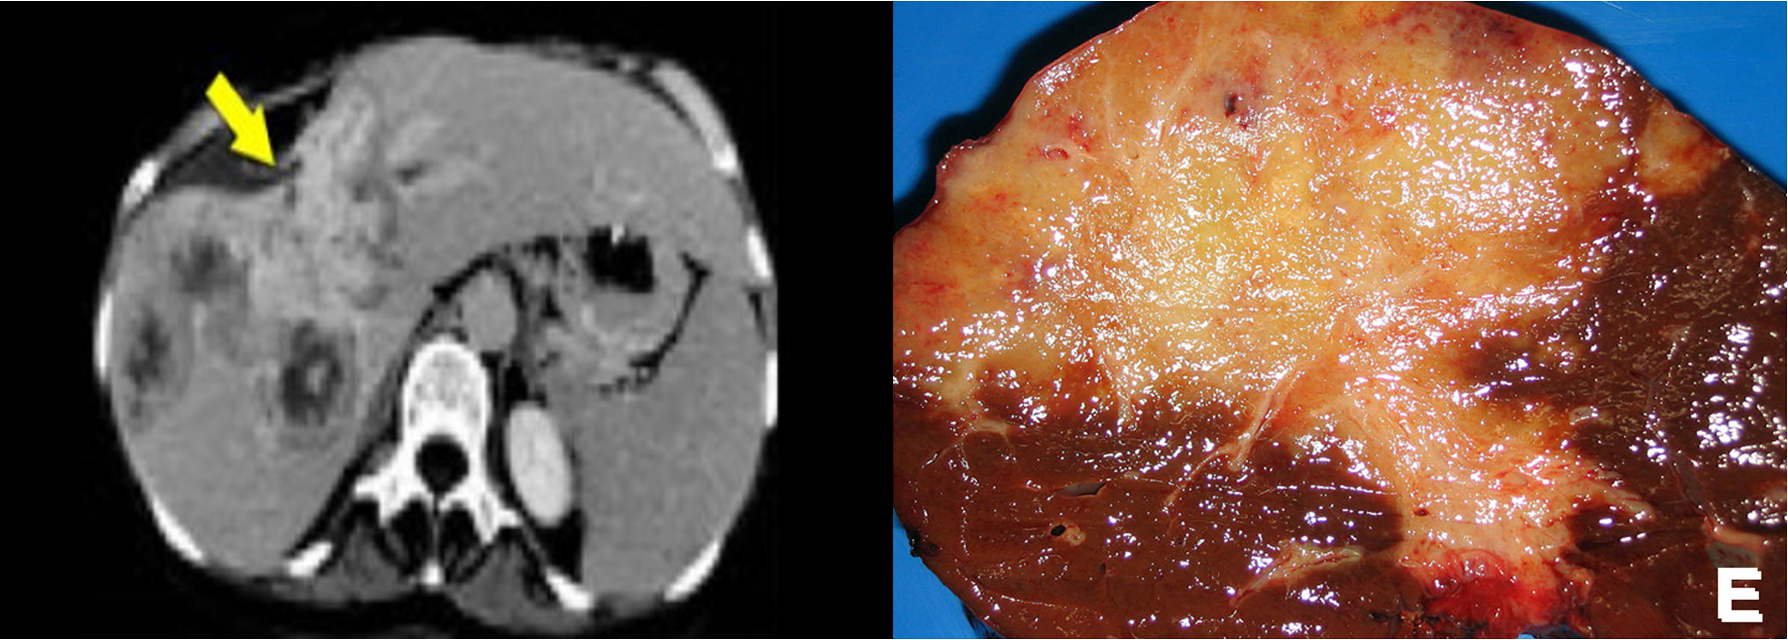

It is adenocarcinoma of intrahepatic biliary radicles.

Cholangiocarcinoma in the right lobe of the liver